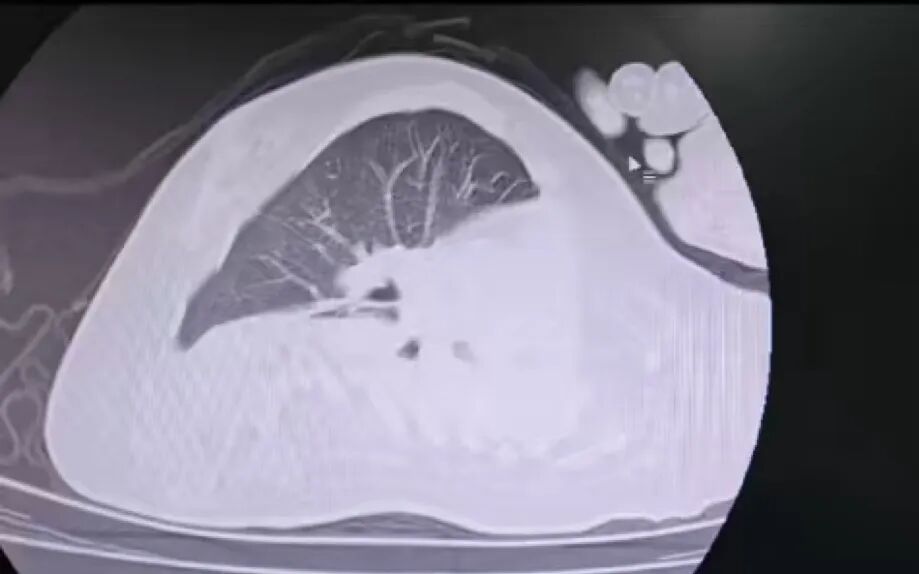

荆楚网(湖北日报)(通讯员:陈芳芳、雷雷)近日,孝感市中心医院儿科团队利用先进技术,成功为患有支气管肺炎、脊髓性肌萎缩症(SMA)、脊柱侧弯等特殊儿童进行了纤维支气管肺泡灌洗。手术后,患者气道阻塞情况明显改善,目前正处于康复后期。 男孩因脊髓性肌萎缩症卧床不起多年。您的呼吸肌明显减弱。自主呼吸微弱,几乎没有咳嗽和痰。这次患上支气管肺炎后,肺部感染迅速恶化,生命垂危。更令人担忧的是,严重的脊柱侧凸会导致儿童出现胸部畸形和气道解剖结构的明显移位。传统的纤维支气管镜进入路线完全无效。缠绕,狭窄的气道看起来就像纵横交错的迷宫。每一次操作都必须精确到毫米级。 姿势放置也是一个“障碍”。除了满足纤维支气管镜的手术要求外,还要避免脊柱侧凸受压,防止肌肉萎缩导致关节脱位。所有角度都必须重复测量。同时,手术过程中我们还要面对多层面的危机。儿童呼吸肌功能大量丧失,纤维支气管镜占据狭窄的气道空间,迅速增加缺氧、二氧化碳潴留、急性呼吸衰竭和心脏骤停的风险。如果清洁过程中残留液体,肺部感染会恶化,孩子的免疫力也会减弱,大大增加败血症的风险。 治疗前 治疗后 为了解决多重危机,儿科团队制定了详细的手术计划。手术当天,百科tric团队在高清内窥镜下小心操作器械,避免扭曲气道结构,准确到达病灶,精心完成冲洗、吸痰等一系列操作。 经过团队的不懈努力,手术终于顺利完成。手术后,孩子生命体征稳定,气道阻塞明显改善并持续好转。 自2019年引进小儿纤维支气管镜技术以来,我们儿科逐步建立了成熟的诊疗体系,并将技术应用拓展到顽固性肺炎、肺不张、气道发育异常、疑似异物吸入等多个领域。目前,我科拥有3名专科医生团队,配备奥林巴斯支气管镜等符合EU 4.0、2.8规格的小儿支气管镜,可满足临床需要。从新生儿到年龄较大的儿童,各个年龄段和各种气道状况的诊断和治疗需求。 迄今为止,京安中心医院儿科已完成约600例小儿支气管镜手术,其中约50例气管异物取出手术。丰富的临床经验使团队在处理复杂病例时能够准确预测风险并快速制定预案,为社区患有呼吸道疾病的儿童筑起一道坚固的防线。